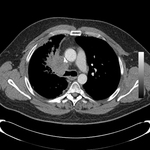

Malignant endobronchial obstruction on multidetector chest CT: lung window demonstrating right mainstem malignant obstruction

From the collections of Jose Fernando Santacruz MD, FCCP, DAABIP and Erik Folch MD, MSc; used with permission